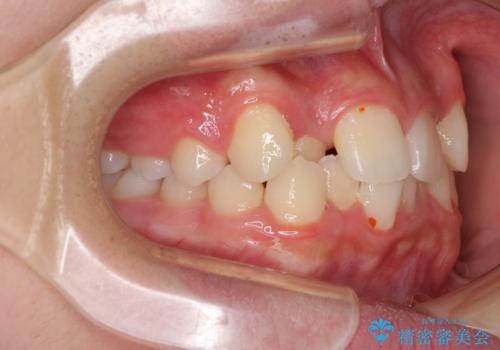

中学生のワイヤー矯正 クロスバイトを短期間で改善

- 前歯のクロスバイトを気にして来院された患者様です。

中学生であることから、治療期間を短縮できると判断し、ワイヤー矯正にて短期間で治療を行うこととしました。

叢生のため磨き残しの多い歯列でしたが、1年弱で治療を終了でき、磨き残しや歯肉の腫れが著しく改善されました。